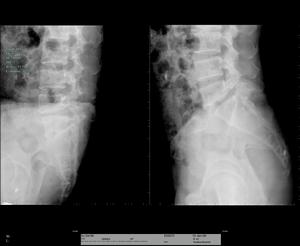

椎管狹窄症正位X線片常顯示腰椎輕度側彎,關節突間關節間距離變小,有退行性改變。側位X線片顯示椎管中央矢狀徑常小,小於15mm就說明有狹窄的可能。必要時可進行腰椎穿刺,奎肯試驗,腦脊液化驗,及脊髓造影。脊髓造影是診斷本症的可靠方法。正位片可清楚顯示硬脊膜腔的大小,如出現有條紋狀或鬚根狀陰影,表示馬尾神經根有受壓現象,或全梗阻,如影柱呈節段性狹窄或中斷,表示為多發性或全梗阻。